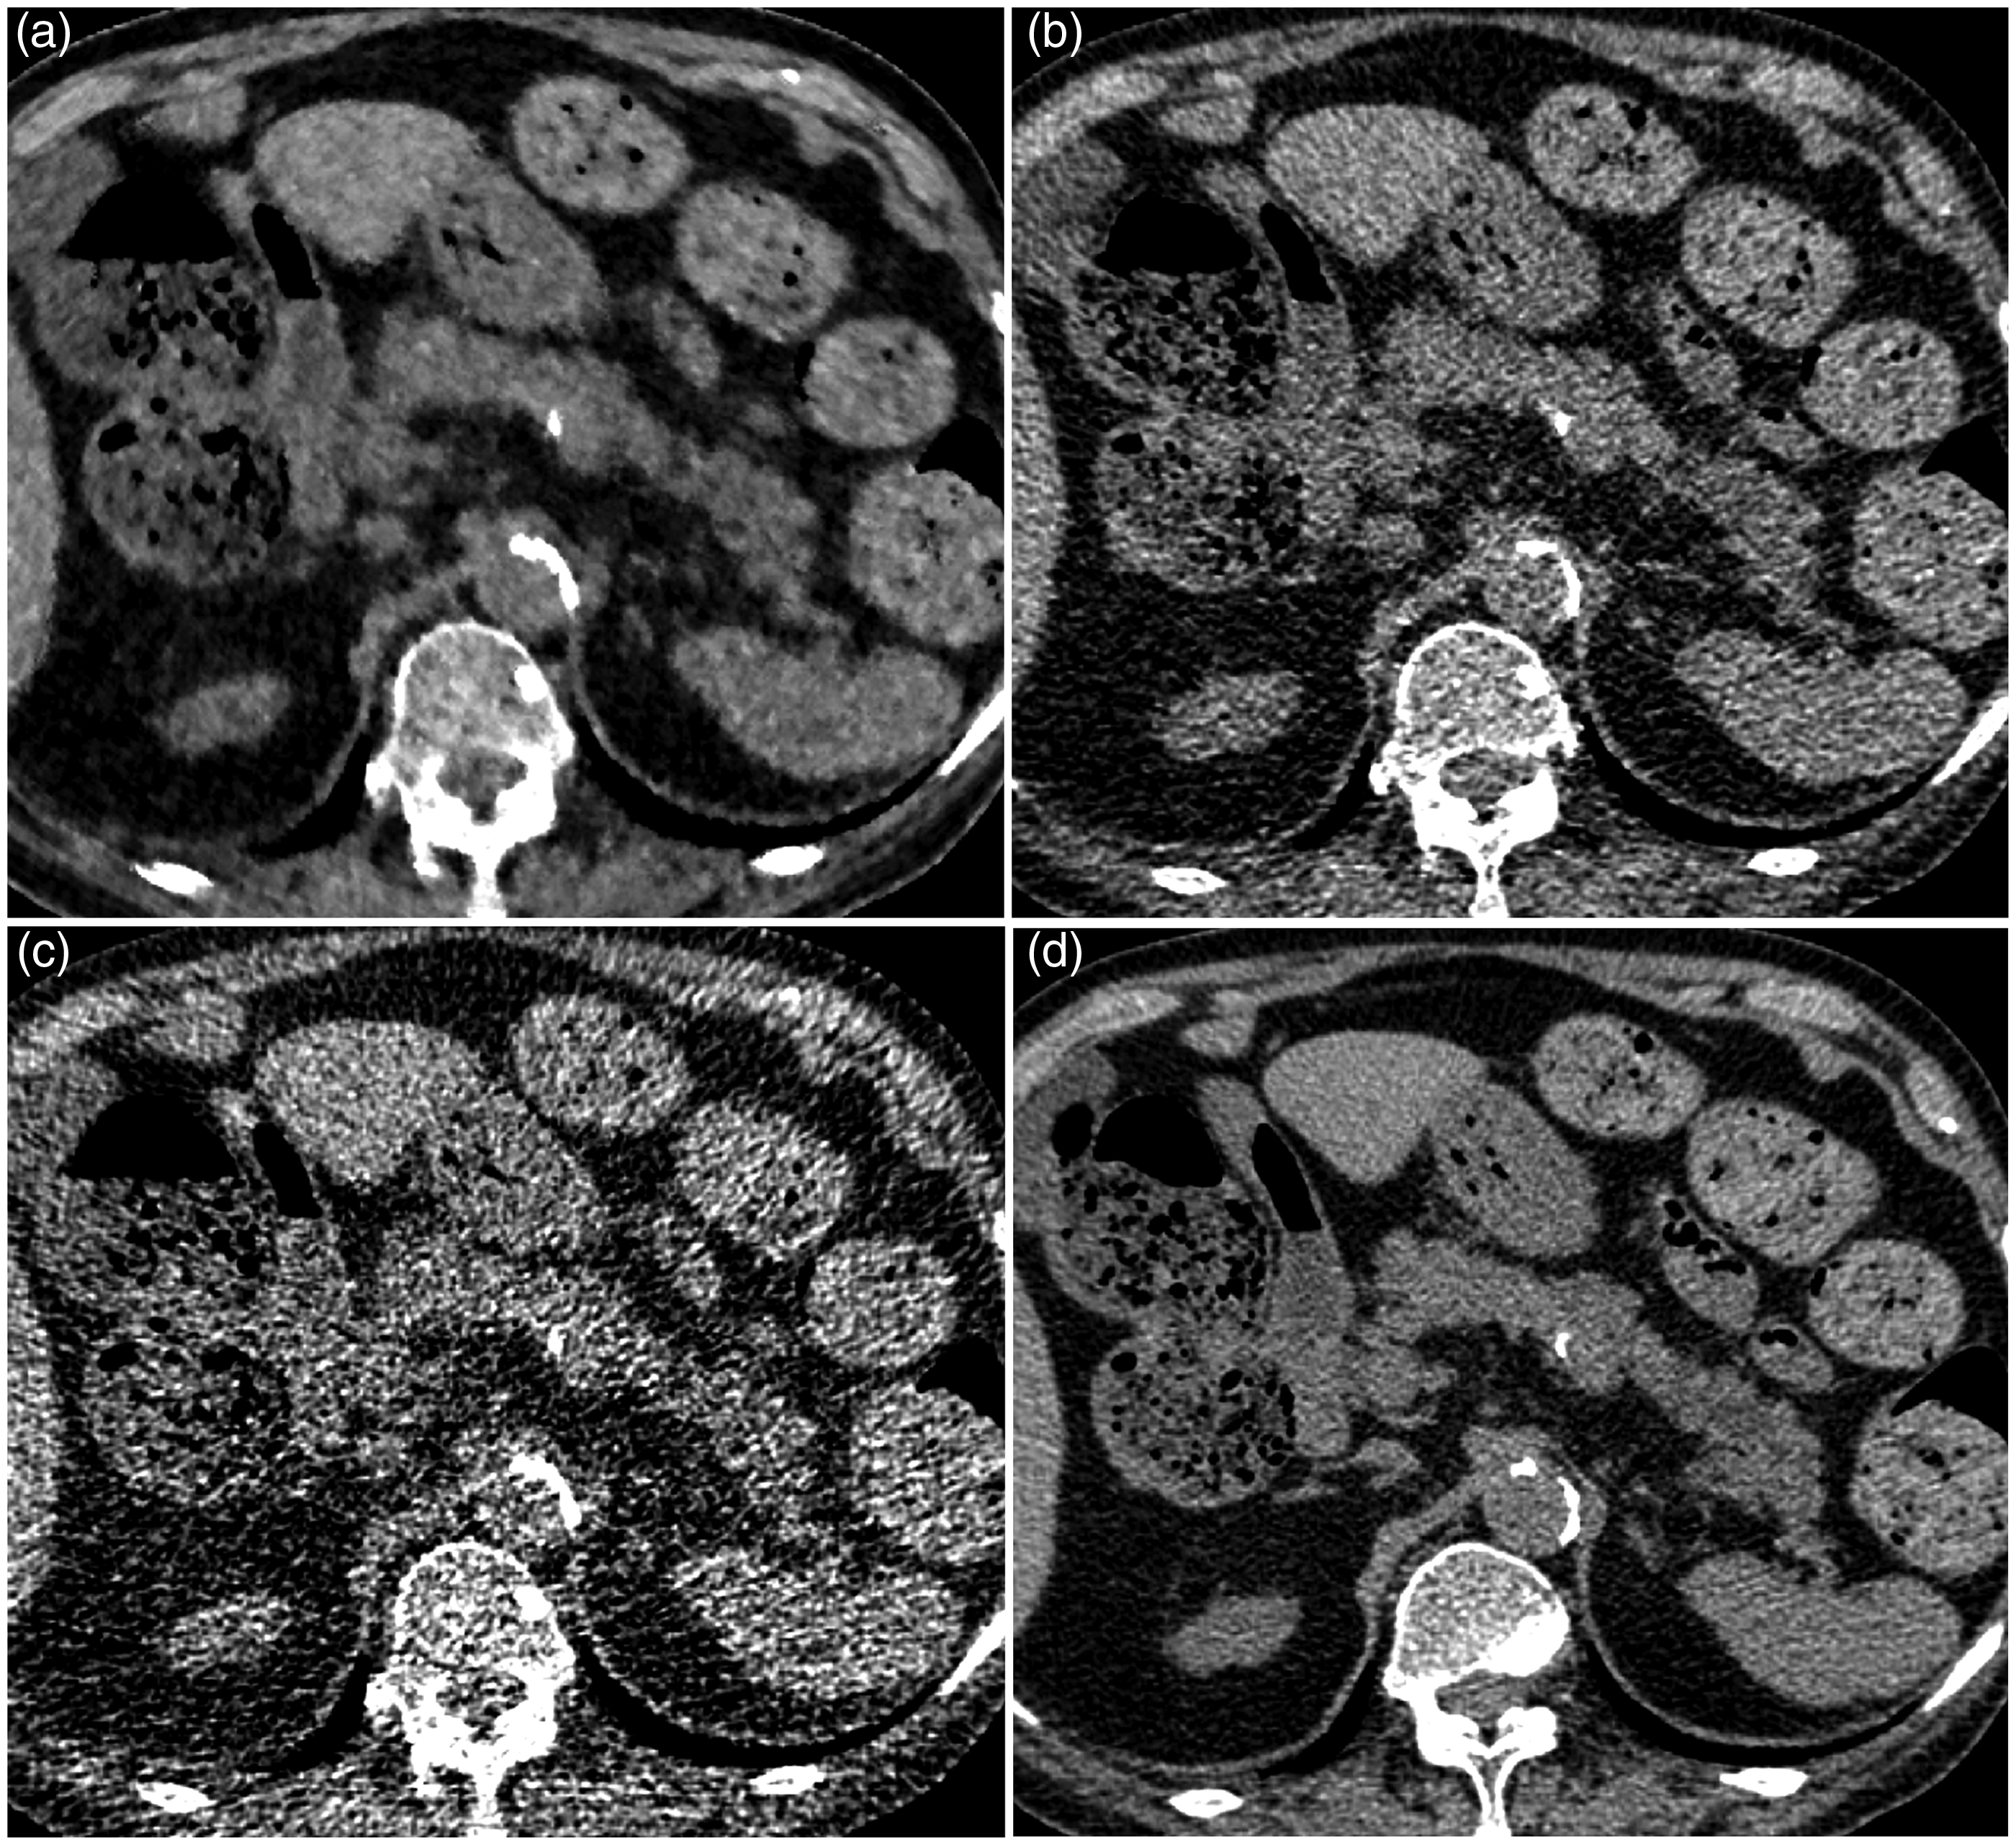

The sensitivity, specificity, accuracy, PPV, and NPV are shown in Table 3. The sensitivity of both readers tended to be high with UL-MBIR (0.67–0.89) compared to L-ASIR and UL-ASIR (0.11–0.44), and a significant difference was seen between UL-MBIR and UL-ASIR for reader 1 ( Axial unenhanced CT images of UL-MBIR (a), L-ASIR (b), UL-ASIR (c), and R-FBP (d) of an 81-year-old woman weighing 60 kg. A calcification of the splenic arterial wall is seen on R-FBP (d), but this patient has no pancreatic calcification. The evaluation score for this patient on UL-MBIR/L-ASIR/UL-ASIR was 2 (calcification probably not present)/2/2 by reader 1 and 4 (calcification probably present)/3 (calcification presence equivocal)/3 by reader 2. It is possible that a calcification of the splenic arterial wall has been misdiagnosed as pancreatic calcification on UL-MBIR (a) by reader 2. Sensitivity, specificity, accuracy, PPV, and NPV for detecting pancreatic calcification. For comparison, McNemar’s test was used. N/A, not applicable; NPV, negative predictive value; PPV, positive predictive value. Receiver operating characteristic analysis results for detecting pancreatic calcification. No significant differences are seen.

The specificity with UL-MBIR was lower than with L-ASIR or UL-ASIR in this study. There might be two reasons for this phenomenon. One is that remarkably reduced image noise resulted in clearer depiction of calcification of the splenic or renal arterial wall, but it was not enough to discriminate pancreatic parenchyma from arterial lumen. Because these mistakable calcifications near pancreatic tissue were not found for some patients, there might be another reason. The other possible reason is that the unfamiliar imaging texture of a blotchy pixelated appearance, which is uniquely seen in images reconstructed with MBIR (17), might also have resulted in false-positive findings. According to Li et al., the shape of noise power spectrum of MBIR is strongly dose-dependent while that of FBP is dose-independent (20). Lower dose leads to noise texture of a relatively coarse graininess with MBIR, which might be related to blotchy pixelated appearance. Some high attenuation area with coarse grain like shape due to dose reduction with MBIR might have been mistakable as coarse faint calcifications of pancreas.